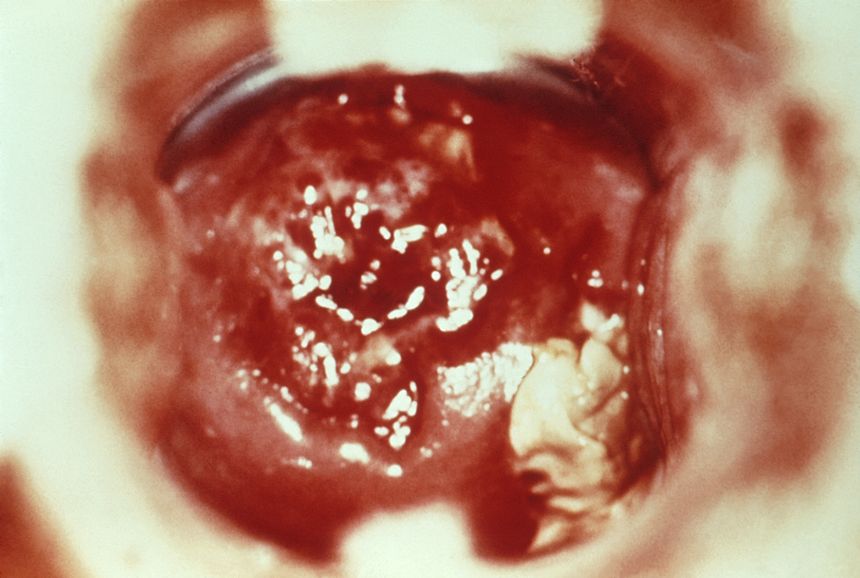

La cervicite est une inflammation du col de l’utérus, également appelé cervix. Le col de l’utérus est la partie inférieure de l’utérus qui s’ouvre dans le vagin. Cette inflammation peut être causée par divers facteurs, tels que des infections, des réactions allergiques, des traumatismes ou des irritations chimiques. Ainsi, la cervicite est souvent associée à des infections sexuellement transmissibles (IST), telles que la chlamydia ou la gonorrhée, mais d’autres agents pathogènes peuvent également être responsables de cette inflammation.

La cervicite est diagnostiquée en présence d’un exsudat cervical (purulent ou mucopurulent) ou en cas de friabilité du col utérin.